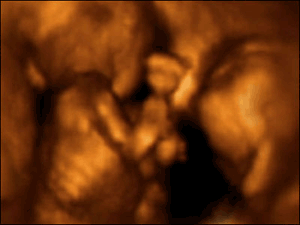

在这里你甚至可以清晰辨认出画面前方这个双胞胎胎儿手上的一根血管。

研究中运用了4-D扫描图像,这些图像通过真实拍摄的3-D扫描图像合成。

4-D扫描图显示了双胞胎在子宫中活动的情况。胎儿为了争夺生存空间和养料而彼此推挤。

有时候,这些推挤看起来像是升级为了相互击打!

这对双胞胎在进行头顶头的肉搏战。